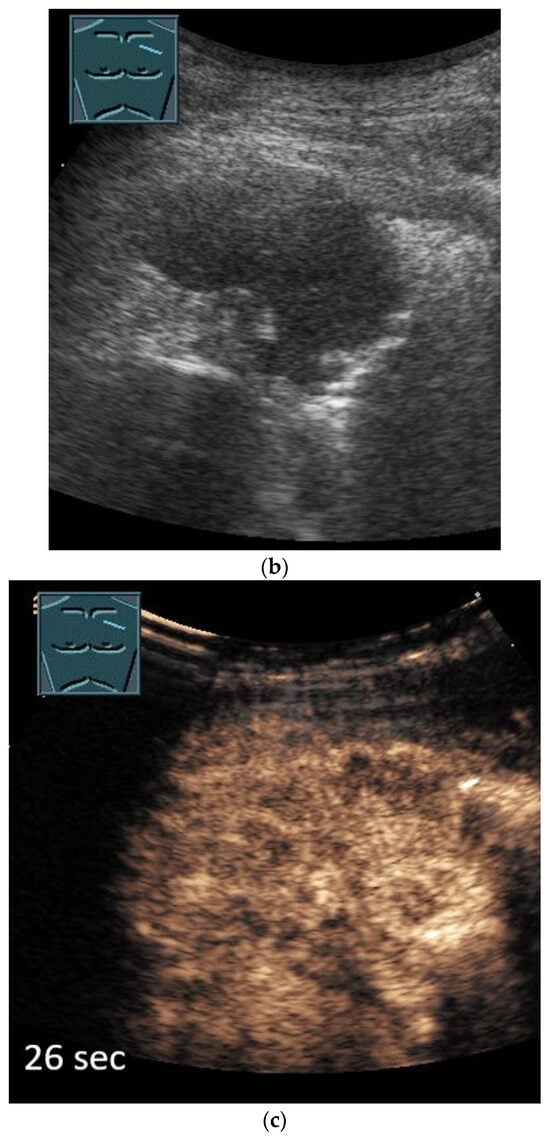

3. Pleural Mesothelioma